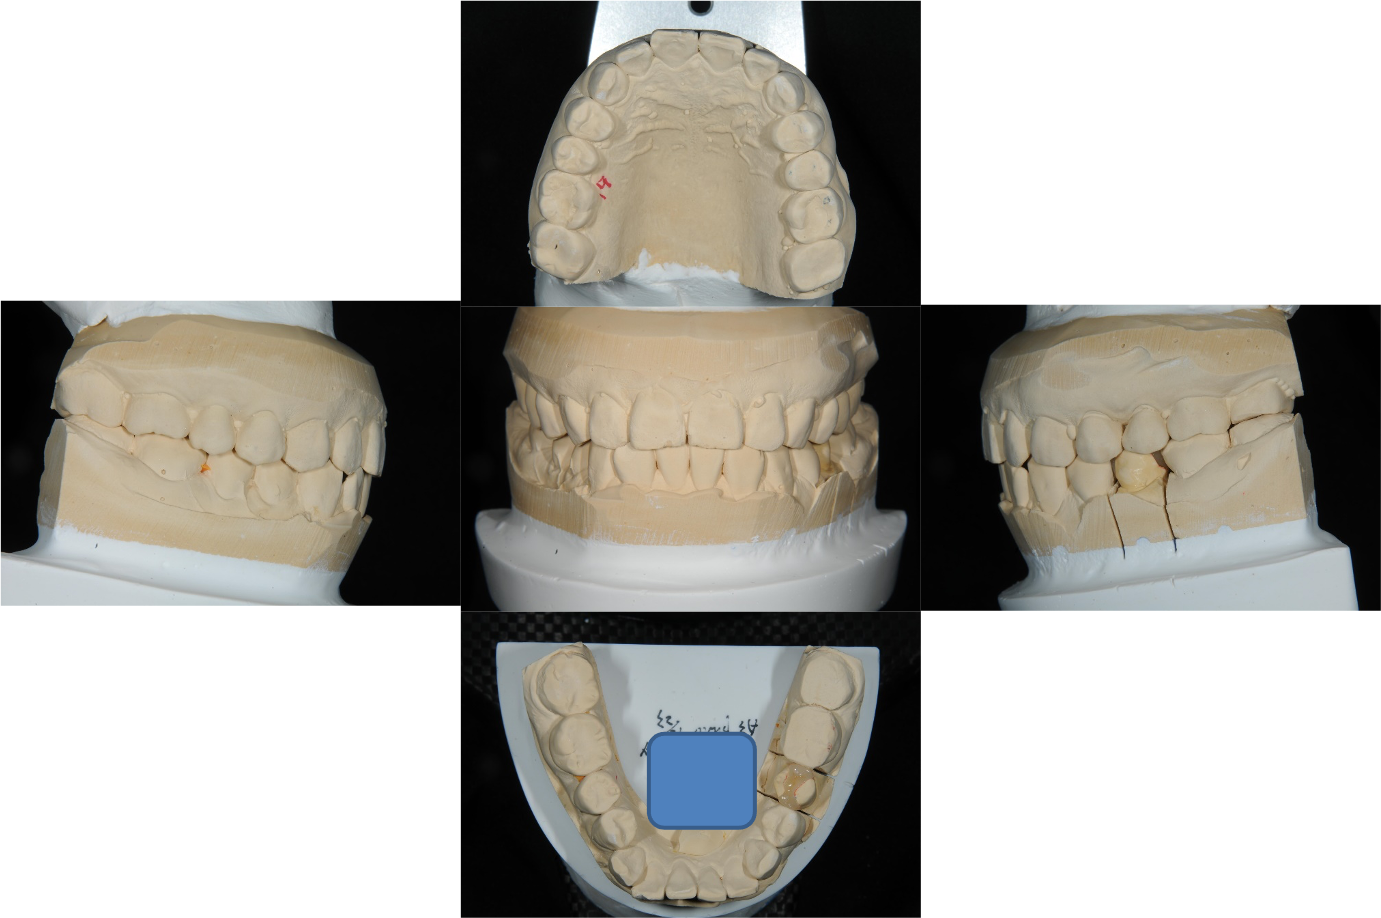

上面弓與咬合器

咬合器上製作瓷塊